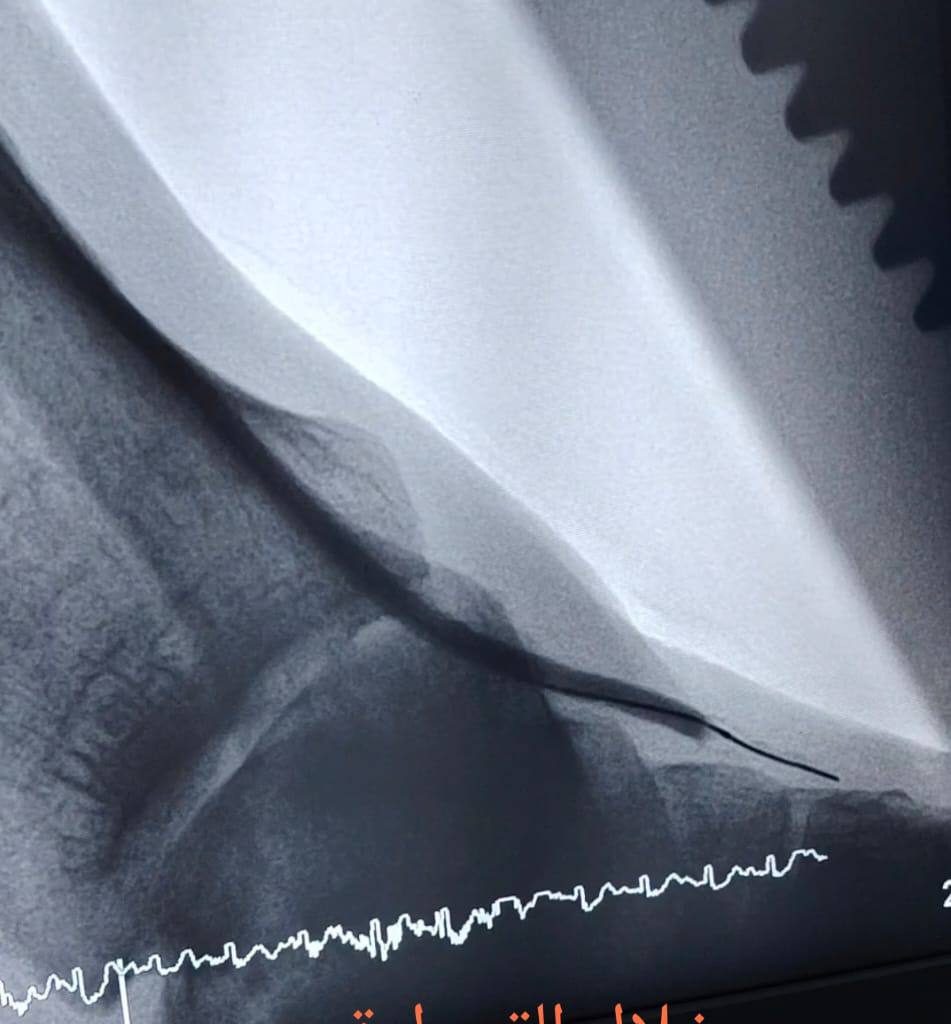

“تم إجراء عمليتين للقسطرة الشريانية، حيث عملنا على فتح الانسدادات في الشرايين الطرفية وعلاج قصور الشرايين، ما ساهم في إعادة جريان الدم إلى الساقين والقدمين بعد أن كانت الحالتان مهددتين بالبتر.”

“الحمد لله، تكللت العمليتان بالنجاح، وتم استعادة التروية الدموية بشكل جيد، الأمر الذي ساعد على إنقاذ الساقين من البتر.”